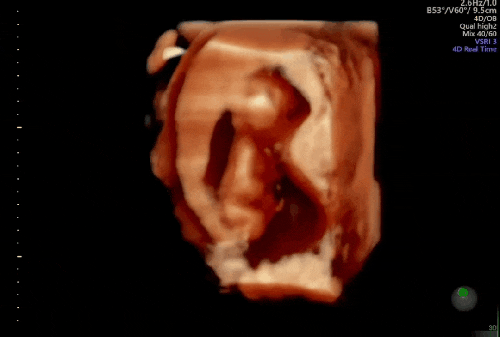

임신 12주 16주/ 1차 2차 기형아 검사

입덧이 심한편은 아니지만 임신전보다 체력도 좋지 않고 제가 좋아하는 맛집 투어도 못 하고 있어요ㅠ 임신...